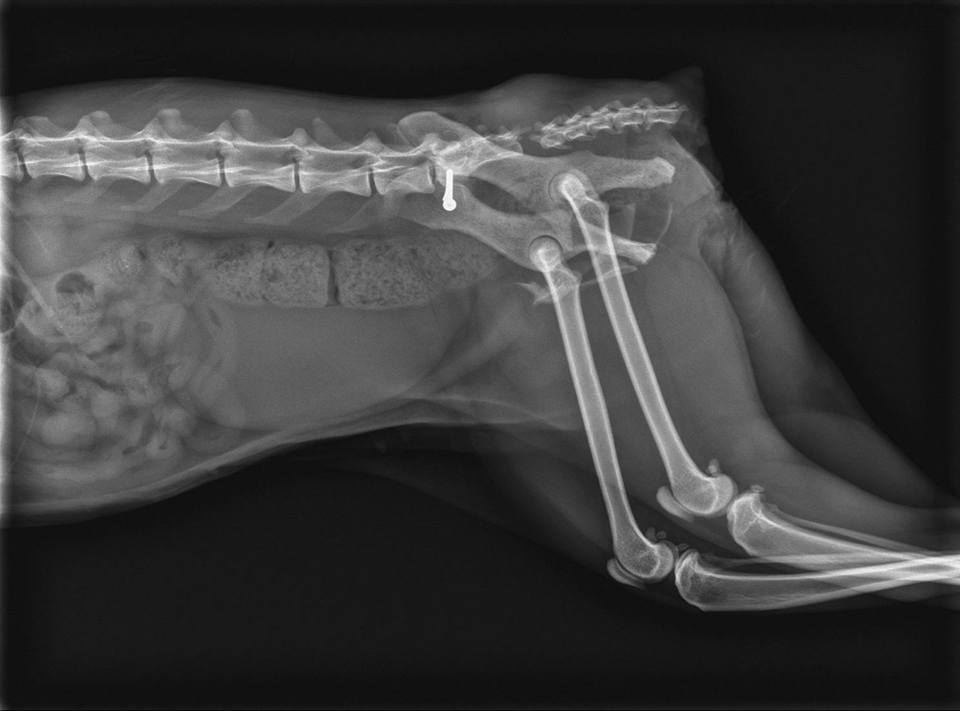

陳醫生由欣旺醫院的X光片解說:

1>貓咪脊椎斷掉的部位是脊椎尾端接尾巴前端的地方//建議將尾巴截掉對斷掉的傷口復原及貓咪往後狀態會比較好

2>貓咪右邊骨盆骨折//骨頭位置移位了//需開刀將骨頭拉回原位置固定住

因X光片無法照出神經方面的問題

陳醫生確定治療前會再補照X光片

因需要貓咪胸腔跟脊椎前段的X光片才能確認進行手術治療